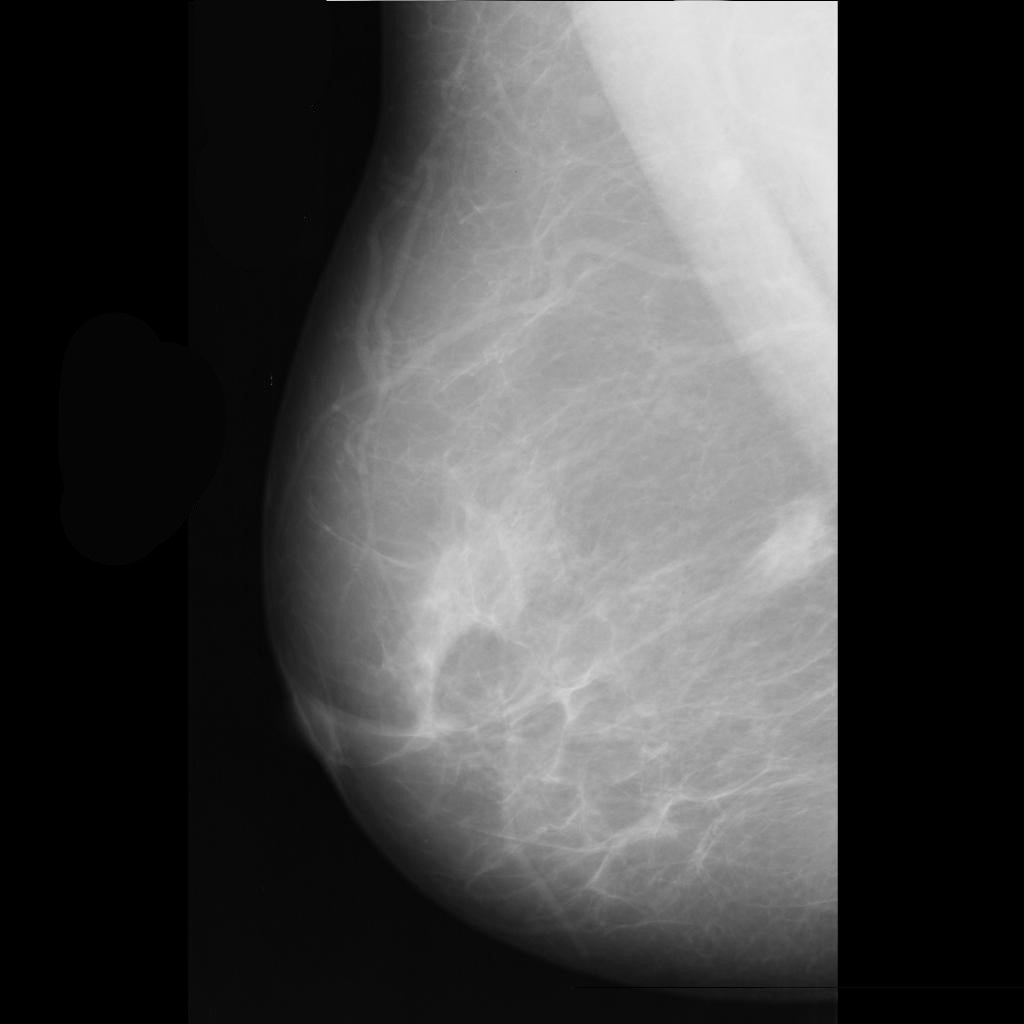

benign